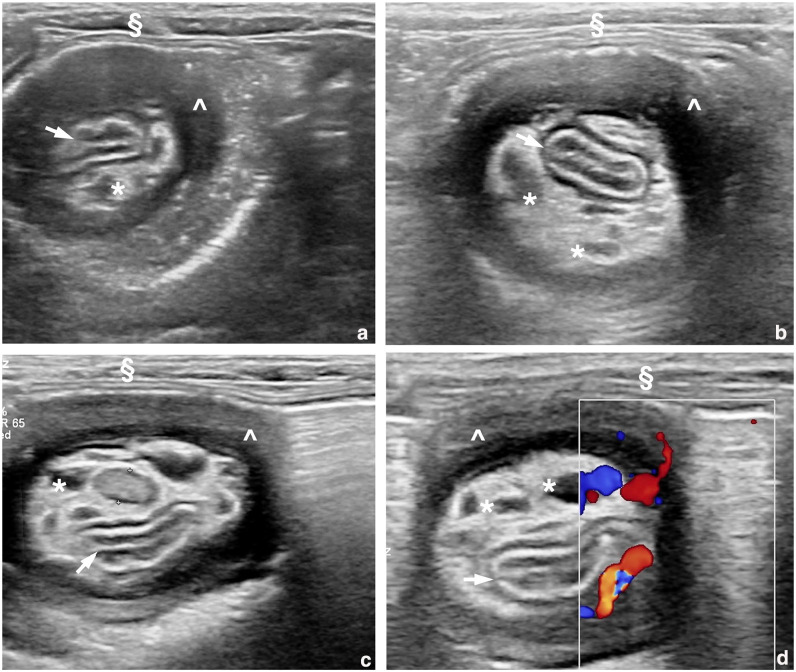

Case summary: A 6-year-old male castrated Maine Coon cat was presented with a 3-day history of lethargy, hyporexia and weight loss. Abdominal ultrasonography demonstrated a double intestinal intussusception with the colon intussuscepting a thickened ileal segment, which was in turn intussuscepting the jejunum. A jejunal prolapse through the anus occurred 3 days later as a complication of the double intussusception, at which time the cat underwent surgery. Manual reduction of part of the intussusception was achieved, while the remaining 30 cm, including of the ileocaecocolic junction, was resected followed by functional end-to-end anastomosis. The cat recovered uneventfully without any reported long-term gastrointestinal complications.

Relevance and novel information: Double intussusception is rare in cats. To the best of the authors' knowledge, this is the first case to describe ultrasonographic features of double intussusception in a cat.